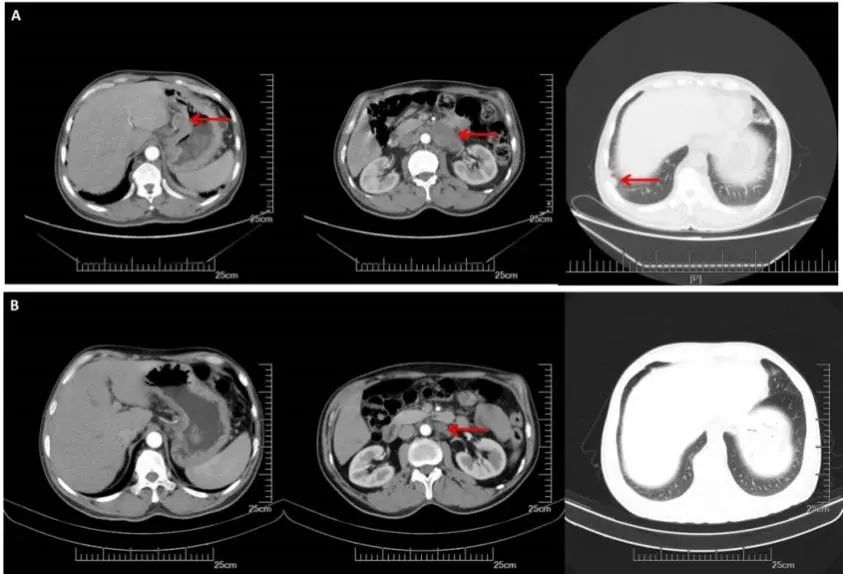

A:CT增强(2016.08.22): 胃体小弯侧增厚,肝胃间、腹膜后多发淋巴结转移,双肺多发转移。B:2周期化疗后CT增强(2016.10.19):胃壁增厚减轻,淋巴结明显缩小,双肺多发转移灶几乎消失